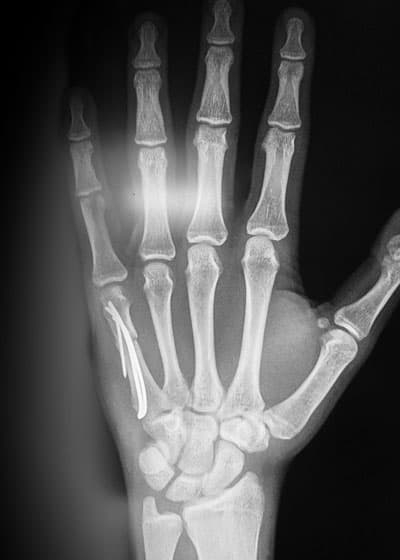

इसके बाद शारीरिक जांच की जायेगी। जैसे आपके हाथ और उंगलियों को जांचा जाएगा। एक्स-रे की मदद से हाथ की तस्वीर भी ली जा सकती है।

बॉक्सर’स फ्रैक्चर के कुछ गंभीर मामलों में सर्जरी कराने की सलाह दी जा सकती है। खासतौर, पर तब जब हड्डियों में एंगुलेशन के लक्षण दिखाई दें। एंगुलेशन के अनुसार उपचार के तरीके भी बदल सकते हैं। माइनर एंगुलेशन में स्पलिंट की आवश्यकता पड़ सकती है, किंतु स्ट्रांग डिग्री के एंगुलेशन में सर्जरी की जरूरत होती है। सर्जरी में पिंस, स्क्रू और प्लेटस की मदद से हड्डी को जोड़ा जाएगा।